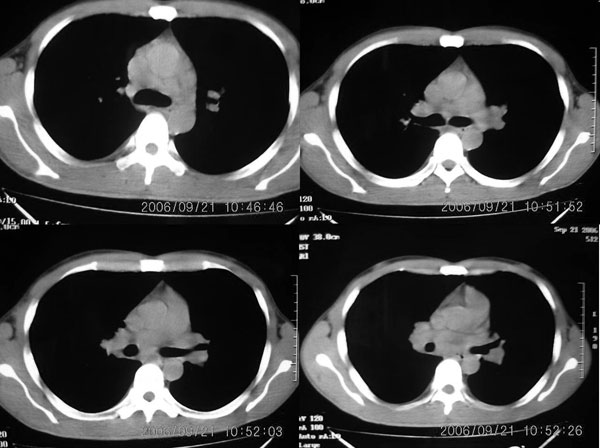

男 27岁 咳嗽一个月,治疗无效。

右肺下叶后段及右肺门附近见斑片状模糊影,密度不均,部分实变,右肺门附近见肿大淋巴结影.

两肺弥漫均匀分部粟粒壮影 右肺基底段不规则软组织密度影其内密度不均 纵隔内淋巴结钟大 请进一步右肺病灶薄层检查及补充病史后再会诊

男 27岁 咳嗽一个月,治疗无效。考虑间质性炎变,右肺下叶后基底段实质炎性结节,伴右侧肺门淋巴结肿大,不除外职业病改变,请高手指点。

右肺下叶后基底段结节样病灶,边界不规则,密度不均,右肺门团片影,肺门增大,纵隔见肿大淋巴结.结合临床首先考虑:肺结核.

图像显示:右下肺门增大,伴右下肺斑片状高密度影,密度不均;右下肺支气管管壁增厚,纵隔内淋巴结肿大。意见:支气管内膜结核、结节病。建议行纤支镜检查。